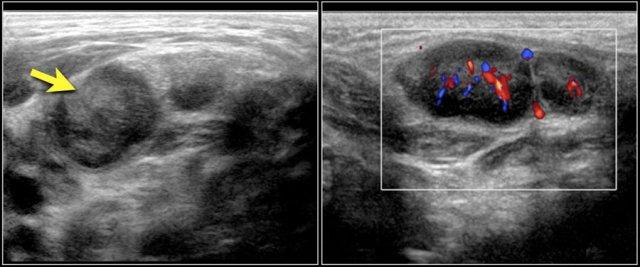

Những hình ảnh này là của một khối u chắc ở cổ của một cô gái 17 tuổi.

Kết quả lấy mẫu tế bào học không có kết luận rõ ràng.

Siêu âm cho thấy hình ảnh điển hình của u vôi hóa biểu mô lành tính (pilomatrixoma), được xác nhận bằng giải phẫu bệnh sau khi cắt bỏ.

Some perfusion in the wall of the pilomatrixoma is seen.